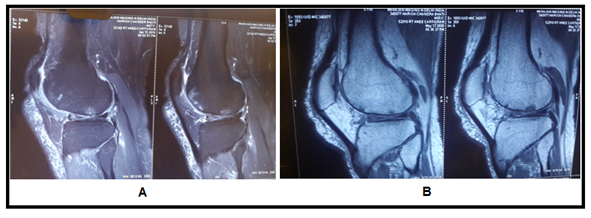

Figure 6 (A) MRI image shows reduced joint space with degenerated cartilage, (B) image shows increase in cartilage thickness.

The MRI study at the last follow−up visit (1 year) showed an important improvement in the cartilaginous tissue in different parameters. Patients showed partial restoration of medial joint space of knee with disappearance of subchondral bone edema with increased thickness of articular cartilage which was more smooth and non porous in contrast to pre BM−MSC transplant stage. The pre and post BM−MNCs transplant MRI/x−Ray studies showed notable changes in cartilage defects (Figures 4‒8).